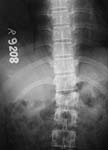

On admission patient was hypotensive. Evaluation revealed him to be having an unstable pelvic ring injury, D12 vertebral body fracture, free fluid in the abdomen and a suspected urinary bladder injury. After his haemodynamic status was better he was taken up for an emergency laparotomy (midline approach). Though there was free blood stained fluid in the peritoneum no hollow viscus injury or other organ damage was noted. Urinary bladder contusion present but no tear. At he same sitting the anterior pelvic ring was stabilised using reconstruction plates through an extended Pfannensteil approach. After a couple of days the posterior ring was stabilised using reconstruction plates (posterior approach). The spine was not interfered surgically since this was inherently stable and there were no neurological findings. The posterior wound grumbled for some time and settled down. He was kept in bed but allowed free turning in bed.

The X rays and few CT reconstructions attached. Kindly give your valuable comments. What all would have been better ways of management?